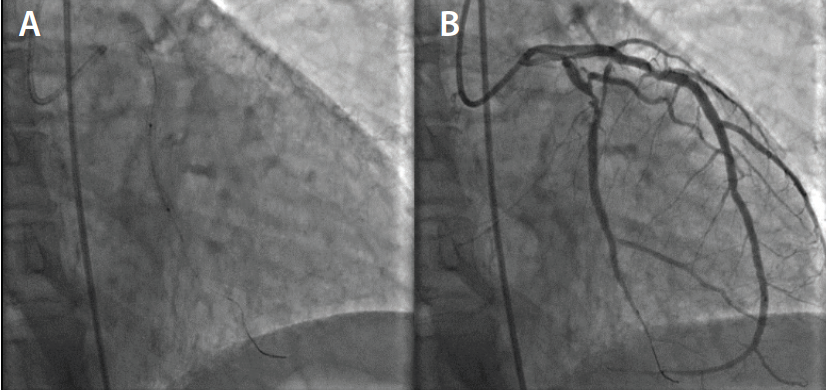

Cardiac catheterization upon her admission demonstrated severe in-stent restenosis of the LMCA, sequential high-grade stenosis (90%) of a tortuous mid–left circumflex artery, and a tandem severe distal circumflex coronary stenosis (Figure 1). These lesions represent a complex interventional challenge with delivery of balloons and stenting to treat the arterial coronary stenosis. The patient was deemed to be a poor candidate for redo CABG and she had failed optimal medical therapy including ß-blockers, long-acting nitrates, and calcium channel blockers.

The decision was made to proceed with percutaneous coronary intervention (PCI) using an extra backup guide and a balanced middle-weight wire (BMW) to cross the lesions in the left circumflex. From the onset of the procedure, the ability to deliver a balloon and subsequent stent appears to be arduous and difficult given the tortuosity and calcification of the left circumflex. With introduction of a Guidezilla™ support catheter (Boston Scientific Corporation), a 2-mm balloon and a 2.5-mm balloon were introduced with difficulty in performing balloon angioplasty. Despite balloon angioplasty, including a high-pressure noncompliant 3.5-mm percutaneous transluminal coronary angioplasty balloon in the left main coronary artery, stent delivery was challenging and complex. The introduction of the EluNIR™ coronary stent system (Medinol Ltd., distributed by Cordis, a Cardinal Health company) allowed adequate pushability and deliverability to cover both the distal-mid–left circumflex artery with two stents. The LMCA was also stented with a 3.5-mm EluNIR™ stent, resulting in an excellent angiographic result (Figure 2). The patient’s postoperative course was uncomplicated and she was discharged home the next day.